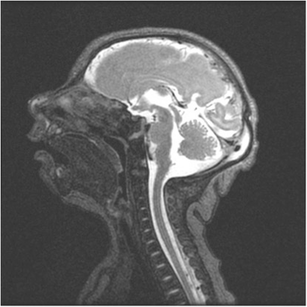

Skull MRI with craniofacial disproportion, increased subarachnoid space, and corpus callosum hypoplasia. The brainstem, cerebellum, and spinal cord are preserved